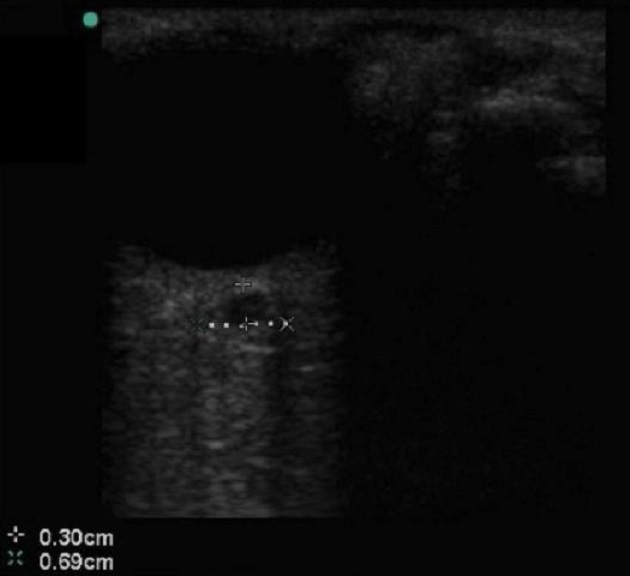

Bild 2: Augen, erweiterter Durchmesser d. Sehnervscheide